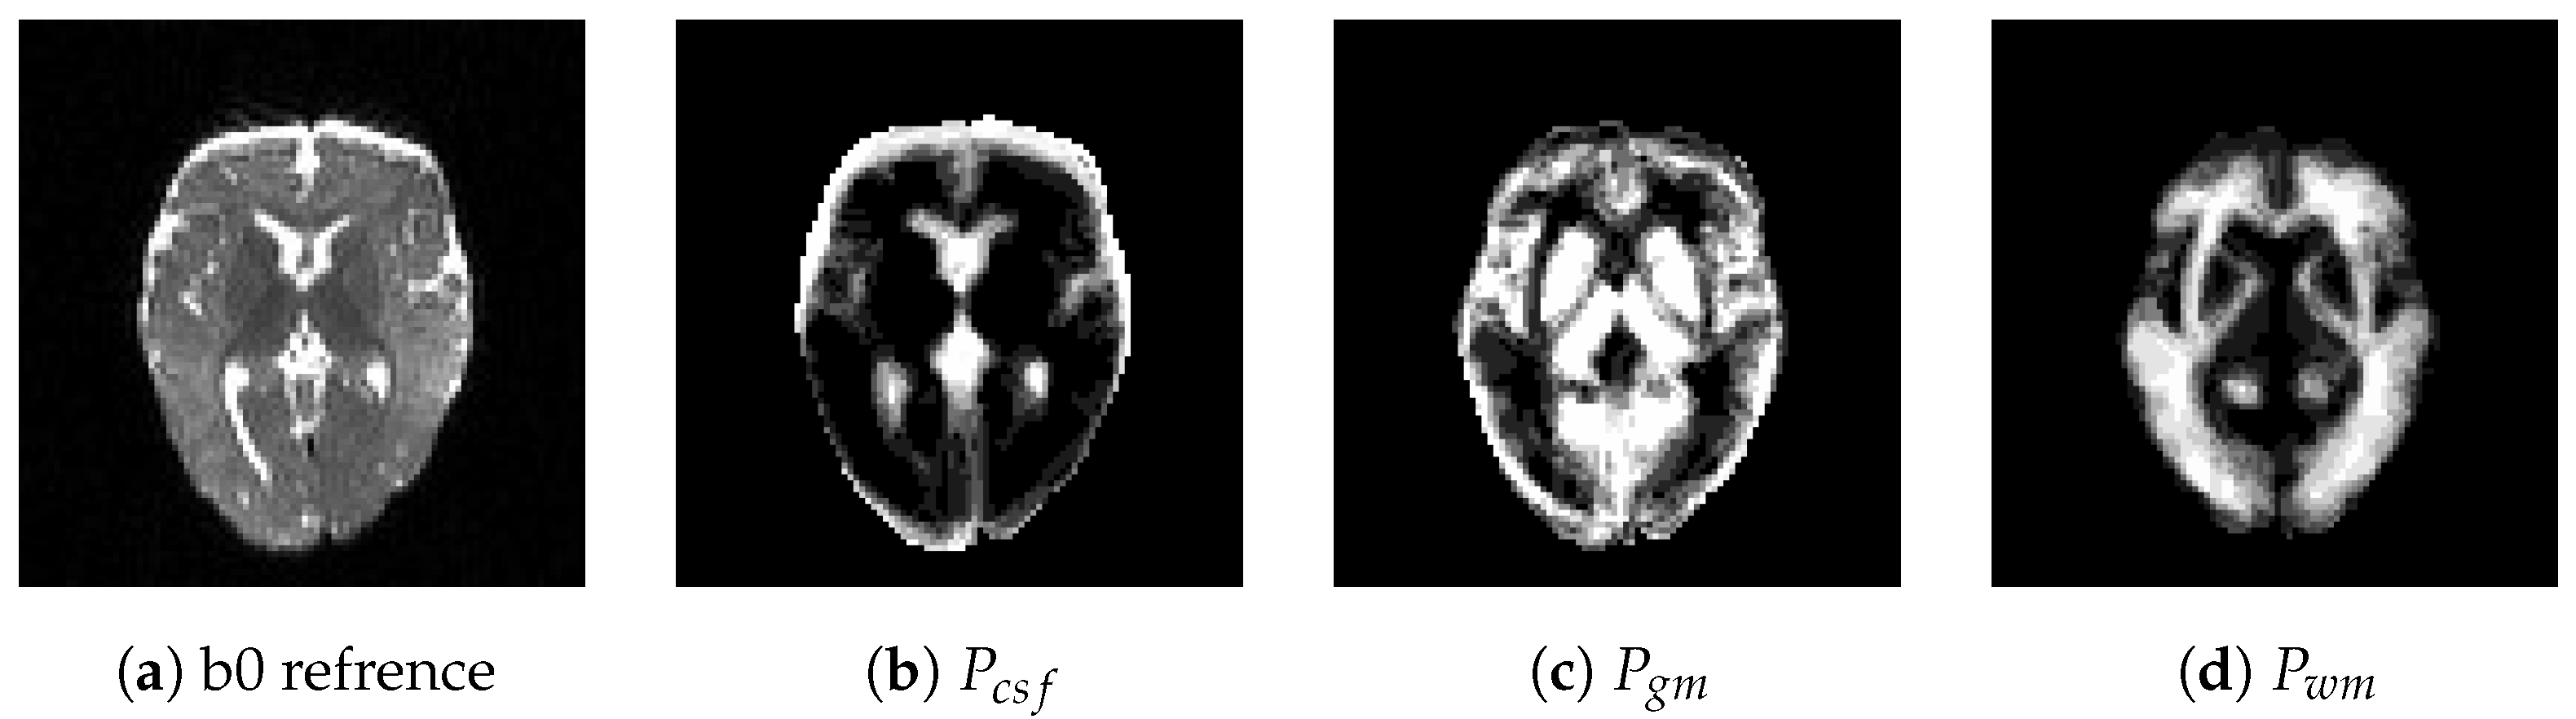

Segmentation Results